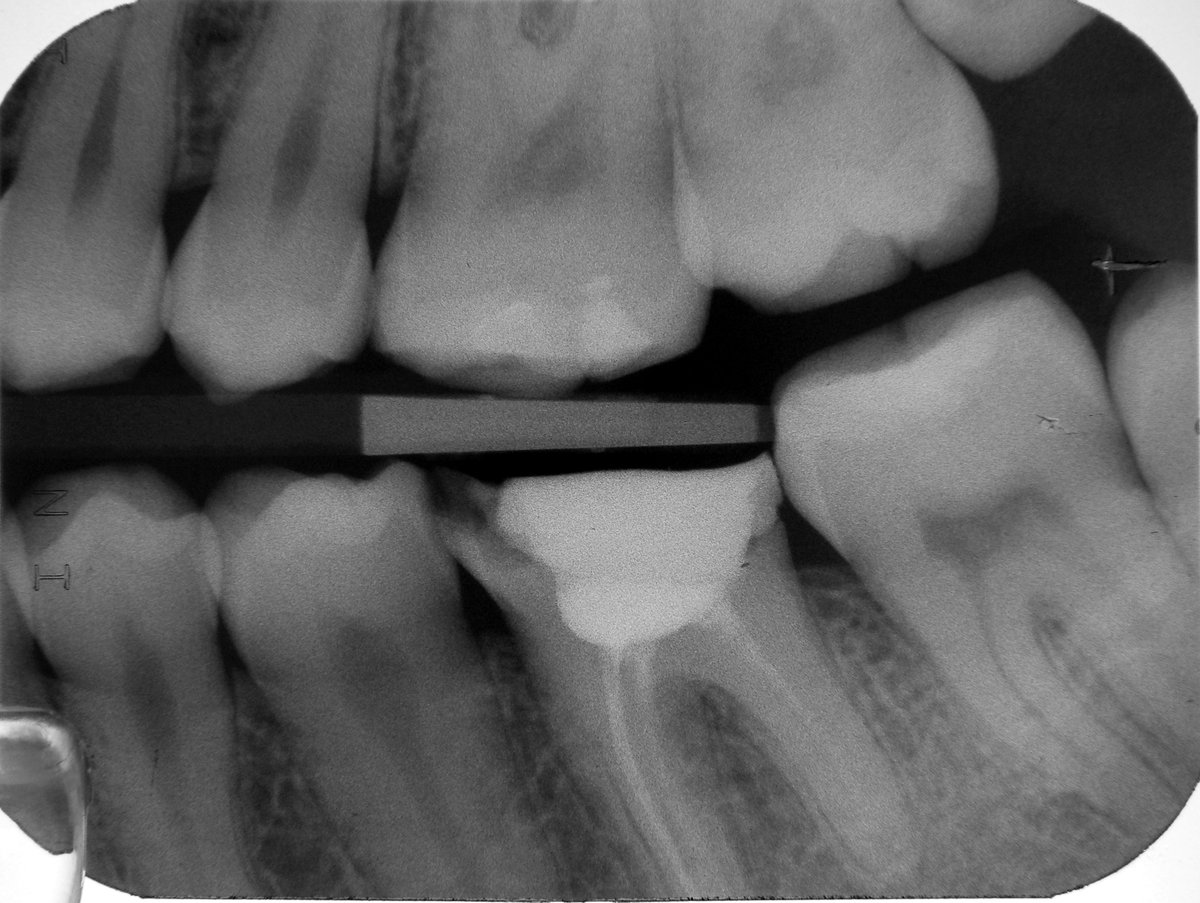

Farbkodierte Guttaperchastifte unterschiedlicher Größen stecken als Wurzelfüllung in den Kanälen.

Das Röntgenbild nach Abschluss zeigt die vollständig gefüllten Wurzelkanäle sowie das in die Kanäle eingepreßte Amalgam zur Verankerung der Füllung.